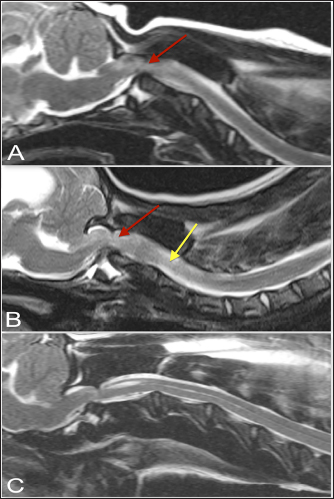

Fig. 1. T2-weighted sagittal (A) and transverse (B, C) images of a 3-year-old spayed female Maltese with acute tetraplegia (TE, 120 ms; TR, 3800 ms; slice thickness, 2.5 mm). On the sagittal image (A), the dorsoventral diameter of the spinal cord at the level of the dens (b) and mid-body of C2 (c) has been measured (red lines), as has the distance from the ventral border of the dens to the caudal articular fovea of the atlas (yellow line). On the transverse images, the cross-sectional area of the spinal cord at the level of the dens (B) and mid-body of C2 (C) has been outlined, as has the subluxation distance from the dens to the atlas (yellow line in B). This dog had dorsally and cranially displaced dens present, as well as an overlapping C1. The transverse ligament was present (white arrow in B).